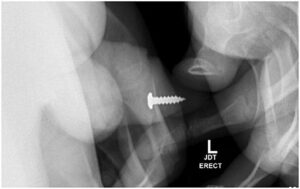

Kasus pertama melibatkan paku, yang dikeluarkan dengan bantuan sistoskop 19fr dan penjepit fleksibel di ruang operasi dengan anestesi umum. Beberapa bulan kemudian, remaja tersebut kembali dengan sekrup logam di uretra, serta mengonsumsi obat hidroksizin. Gejala utama berupa retensi urine dan nyeri penis.

Seorang remaja berusia 17 tahun memasukkan sekrup ke dalam uretranya sendiri. Tak hanya sekali, ia memasukkan total 20 kali hingga dilarikan ke UGD. Foto: Adam Bezinque/ jurnal Frontiers In.

Pada satu kunjungan, sekrup ditempatkan di uretra distal, dengan ujung tumpul diarahkan keluar terlebih dahulu. Tim medis melakukan observasi konservatif dan uji coba berkemih. Hasilnya, pasien dapat mengeluarkan 1 liter urine dengan benda asing tersebut tanpa komplikasi.